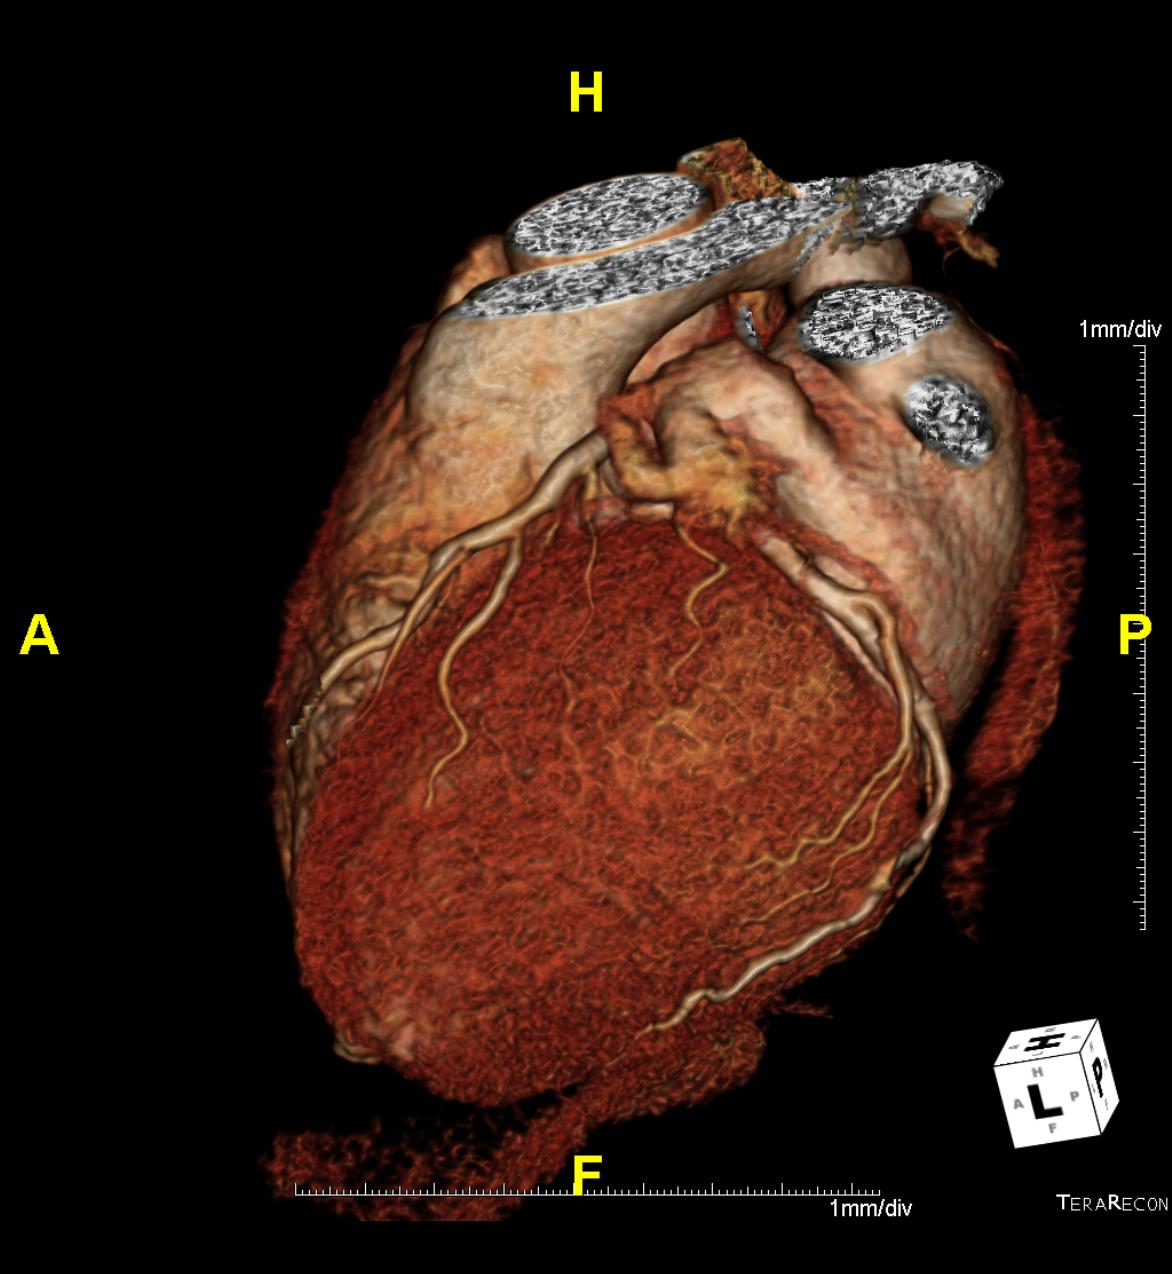

Das Klinikum Ludwigshafen verfügt über einen Kardio-CT der neuesten Generation: Das 128-Zeilen-Gerät ermöglicht eine äußerst präzise Untersuchungsmethode zur Darstellung der Herzkranzgefäße des schlagenden Herzens.

Die koronare Herzerkrankung (KHK) ist eine der häufigsten Erkrankungen in der westlichen Welt. Bei dieser Erkrankung führen Kalkablagerungen an der Gefäßwand (Arteriosklerose) zur Verengung des betroffenen Gefäßes. Diese Engstellen (Stenosen) vermindern die Blutversorgung des Herzmuskels. Kommt es mit dem Fortschreiten der KHK zum Gefäßverschluss, entsteht ein Herzinfarkt.

Die Computertomografie des Herzens (Kardio-CT) ist eine Methode, die frühen Stadien der KHK zu erkennen, bzw. eine KHK mit an Sicherheit grenzender Wahrscheinlichkeit ausschließen zu können.

Prinzipiell ist die Kardio-CT eine Computertomografie (CT), also eine Röntgenuntersuchung, bei der die Röntgenröhre spiralartig um den Patient rotiert. Das Besondere ist die enorme Leistungsfähigkeit der CT, bei der mehrere, sehr dünne Schichten pro Umdrehung gleichzeitig aufgenommen werden.

In Ludwigshafen verwenden wir einen CT der neuesten Generation der Firma Siemens, mit dem wir 128 Schichten pro Umdrehung aufnehmen. Auf diese Weise lässt sich das gesamte Herz mit nur vier bis fünf Umdrehungen erfassen. Für Sie bedeutet das, dass wir Ihre Herzkranzgefäße in der derzeit bestmöglichen Auflösung und mit geringst möglicher Strahlenbelastung darstellen können.

Auf dem Untersuchungstisch werden EKG-Elektroden angeschlossen. Dadurch kann sich der CT an Ihren individuellen Herzschlag anpassen.

Während der wenige Sekunden dauernden, eigentlichen Untersuchung müssen Sie kurz die Luft anhalten. Das ist nötig, da das Herz genau auf dem großen Atemmuskel, dem Zwerchfell, liegt und daher beim Atmen stark auf und ab bewegt wird.